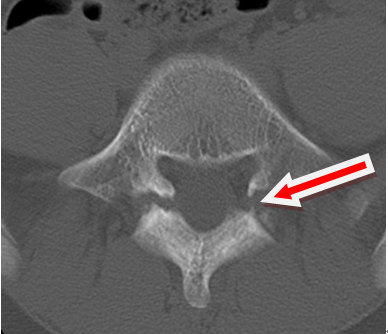

术前ct显示峡部裂

ct看椎弓根峡部裂